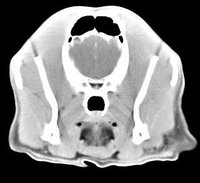

imágenes de TC en el perro | ||||||||||

ejemplo de imágenes de TC en el perro. Nótese la celulitis en la región parotídea izquierda | ||||||||||